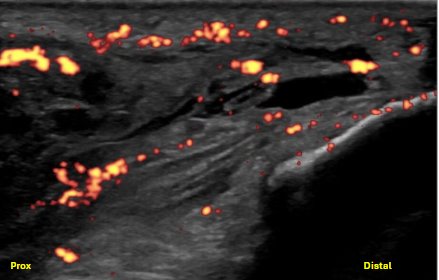

Power Doppler imaging reveals increased peritendinous and intra-tendinous hyperemia at the site of fiber disruption.

Unlabeled long axis view of the posterior elbow with power Doppler